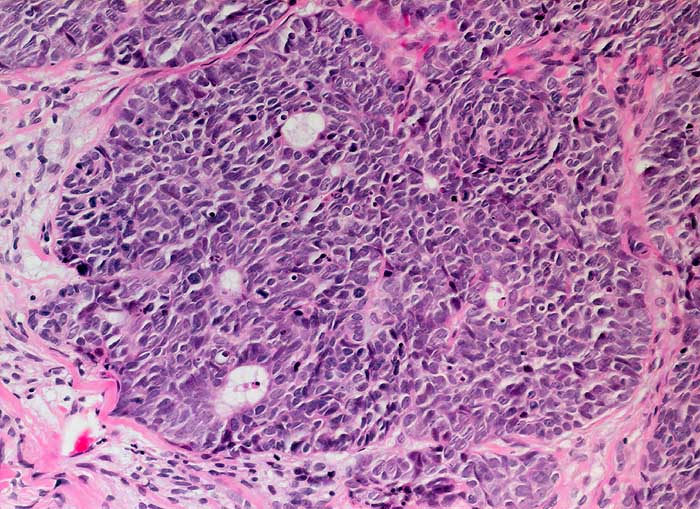

PathoPic ID 6204 - basaloides Plattenepithelkarzinom

basaloides Plattenepithelkarzinom

maligner Tumor

Portio

Genitalorgane, weiblich

Basaloid differenziertes Plattenepithelkarzinom. Die Tumorzellen erinnern an die Zellen eines grosszellig neuroendokrinen Karzinoms.

polypöser Tumor der Zervix

Histologie

200